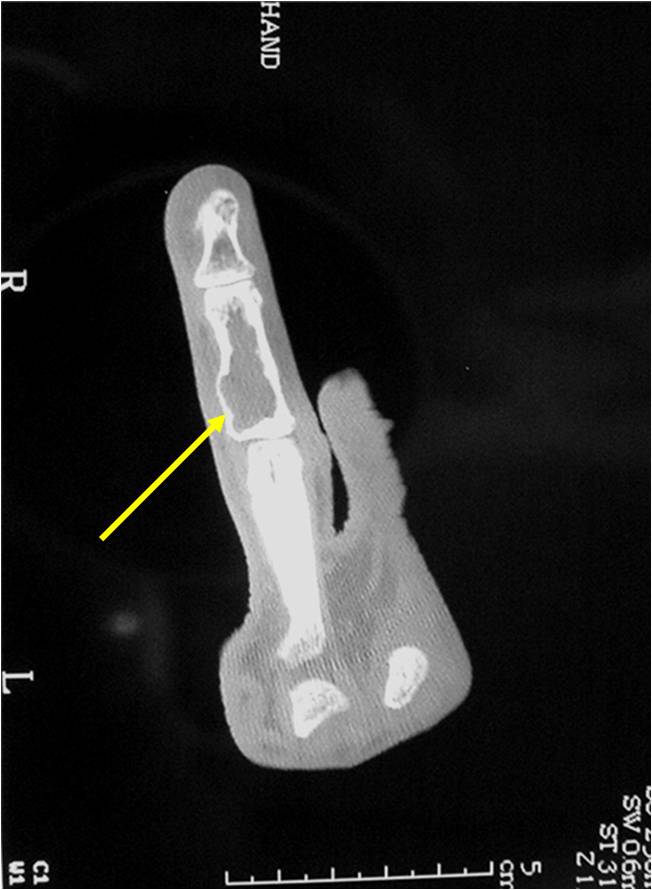

- 50% involve hands and feet (mostly phalanges)

- Cortex may be scalloped and thinned in the phalanges

- Expansile remodeling with thinned cortex

- Enchondromas of digits can have hypercellularity, bi and trinucleated cells and myxoid change and still be considered benign

- Digits: Impending or actual pathological fracture

- Intralesional curettage and bone graft or cement